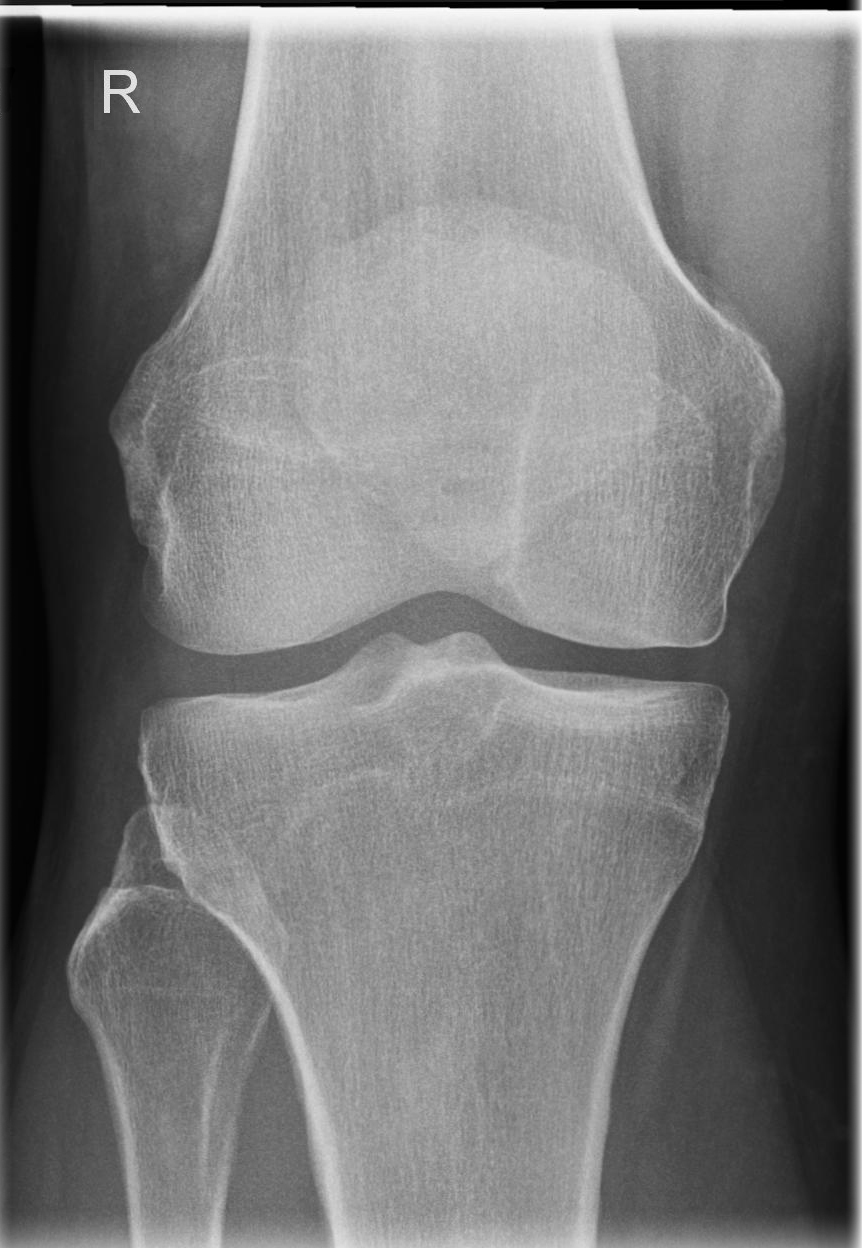

Knie a.-p (1. Ebene)

Fraktur, Luxation, entzündliche und degenerative Veränderungen

Kniegelenkspalt muss frei abgebildet sein, Tibiaplateau lateral muss strichförmig dargestellt werden, medial leicht oval, Kniescheibe mittelständig.